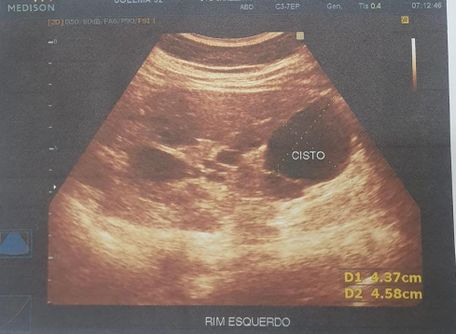

Foi realizado exame de imagem (21/10/2024), ultrassonografia abdominal com os seguintes achados (figura 1.1, 1.2, 2 e 3) Exames laboratoriais (21/10/2024): Acido úrico 2 mg/dl, Bilirrubina total 0,37 mg/dl, Bilirrubina direta 0,18 mg/dl, Bilirrubina indireta 0,19 mg/dl, TGP 21 u/l, TGO 16 U/L, Uréia 34 mg/dl, Creatinina 0,51 mg/dl, Sorologia para hepatite B, C não reagente.

Figura 2.

Figura 2 e 3. Rim esquerdo ,apresenta tamanho aumentado , parenquima heterogêneo e contornos irregulares, com dimensoes 13.1 cm x 5.3 cm. Multiplos cistos em ambos os rins, o maior no polo inferior do esquerdo medindo 4.6 cm x 4.4 cm. Rim direito , apresenta tamanho aumentado, parenquima heterogêneo e contornos irregulares, dimensoes 12.0 cm x 5.1 cm.